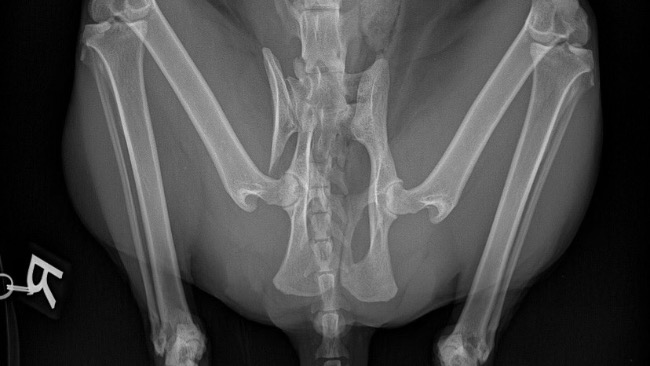

Niestety, niedawno Cynamon był ofiarą wypadku samochodowego, który spowodował poważne złamanie miednicy. Obecnie potrzebuje on pilnej operacji, aby odzyskać zdrowie. Jego cierpienie jest dla nas ogromnie trudne do zniesienia, i chcielibyśmy dać mu szansę na pełne życie i długie, szczęśliwe lata razem z nami.